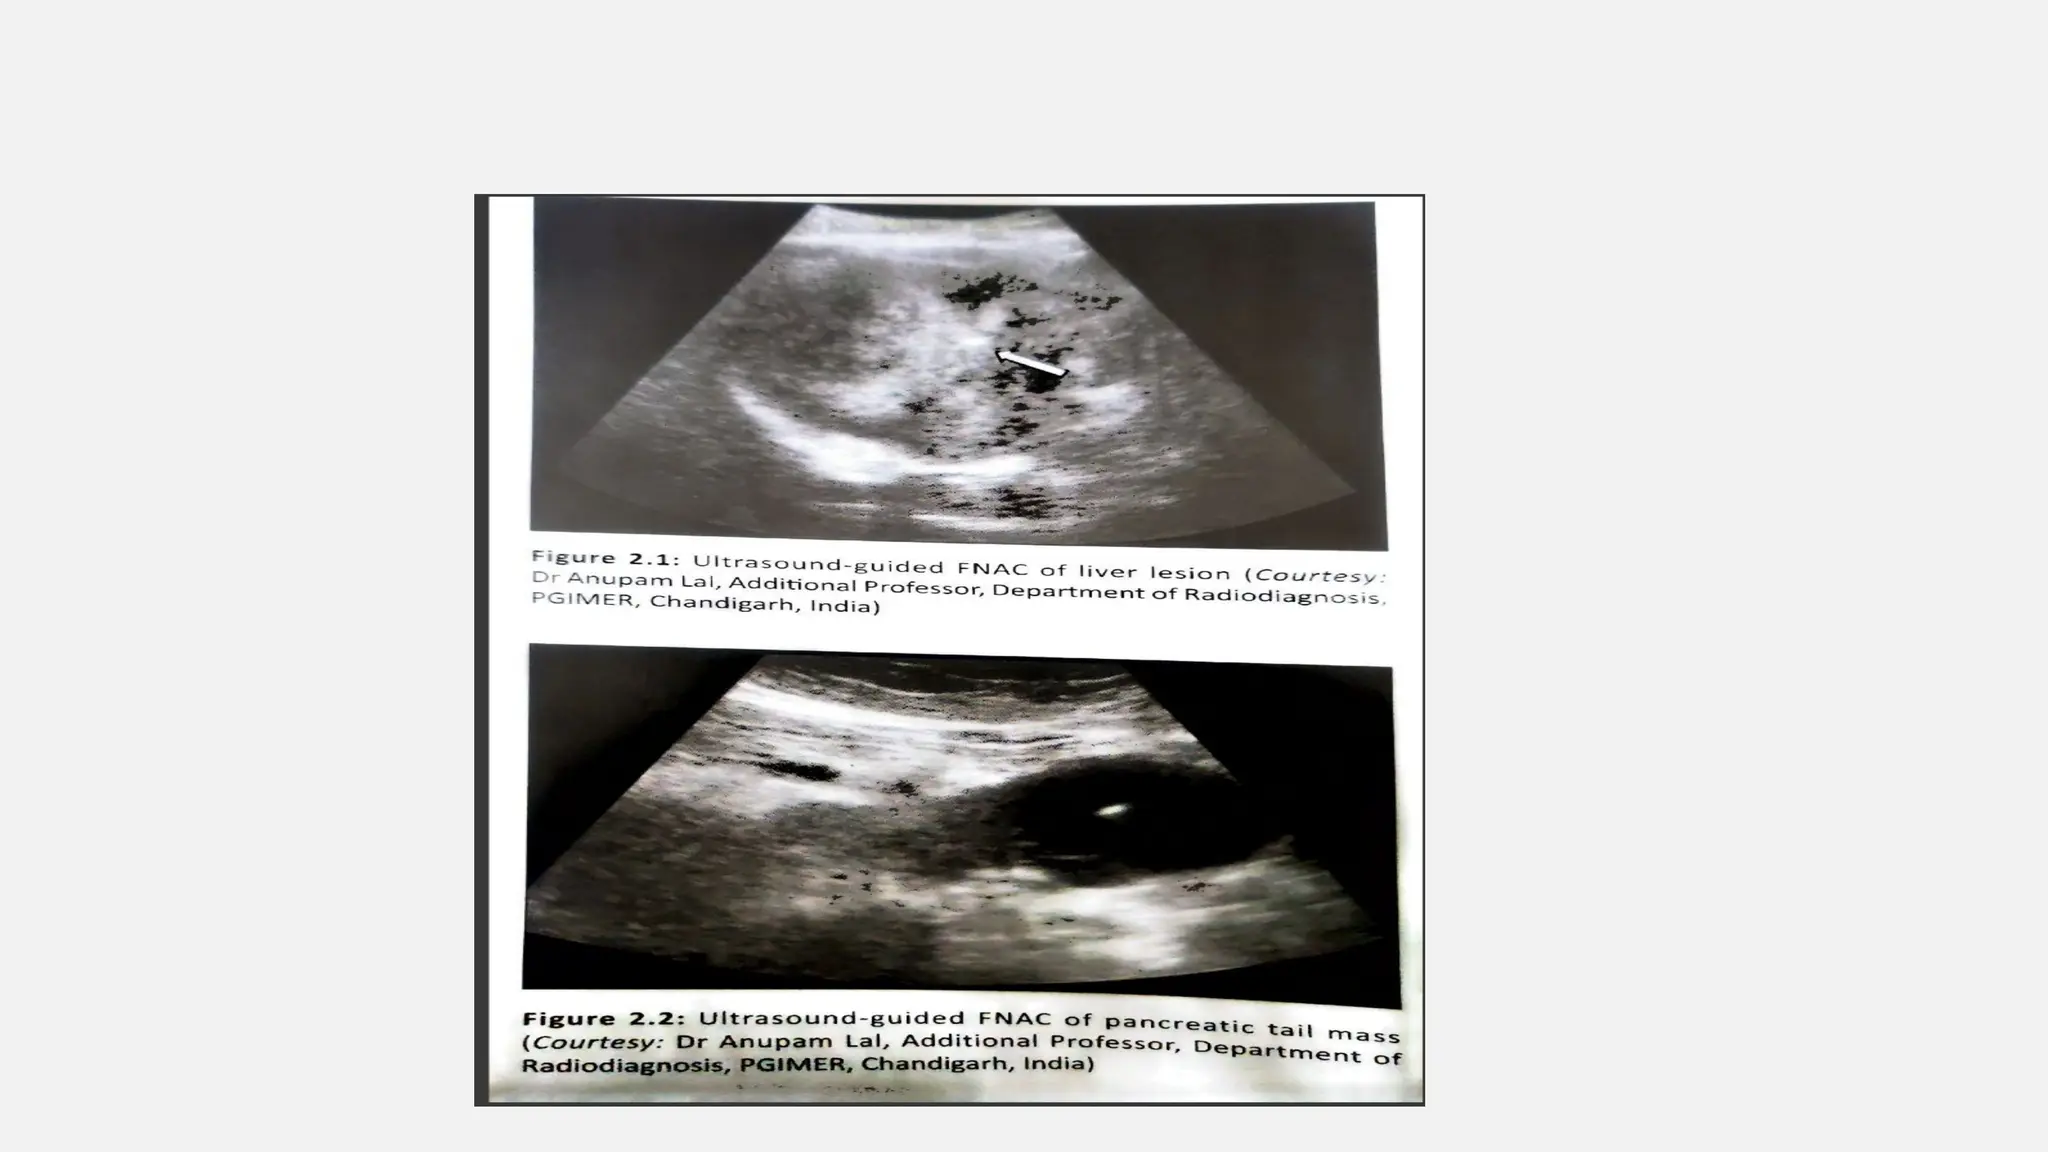

USG GUIDED FNAC

Principle: high frequency sound wave is applied and the reflection of

the wave from tissue interface is recorded to construct image.

Advantage:

• Economic, portable, rapid, easy to do, real time.

Disadvantage:

• Significant obscuration due to air or bone may affect the image.

• Operator dependent

• Not of high resolution.

Application: almost all the body lesion except bony lesion.